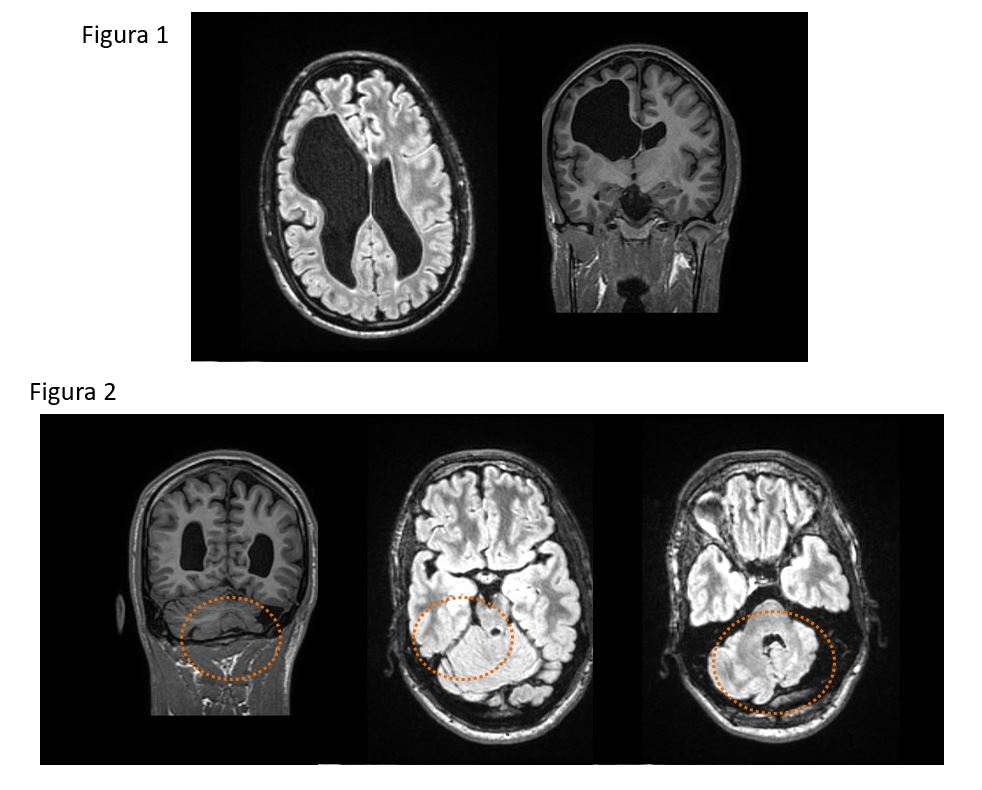

FIGURA 1 : Estudio de RM 1,5T, donde se muestra 1)corte axial de cerebro con secuencia FLAIR 2) corte coronal con secuencia FSPGR 3D . Se observa asimetría ventricular con cavidad porencefálica derecha. No se identifican otras alteraciones significativas.

FIGURA 2: 1.Plano coronal con con secuencia FSPGR 3D. 2 y 3. Planos axiales con secuencia FLAIR.

Como hallazgo secundario, se identifican un pedúnculo cerebral derecho más pequeño, así como un hemisferio cerebeloso controlateral de menor tamaño. Estos hallazgos son compatibles con diasquisis cerebelosa cruzada.